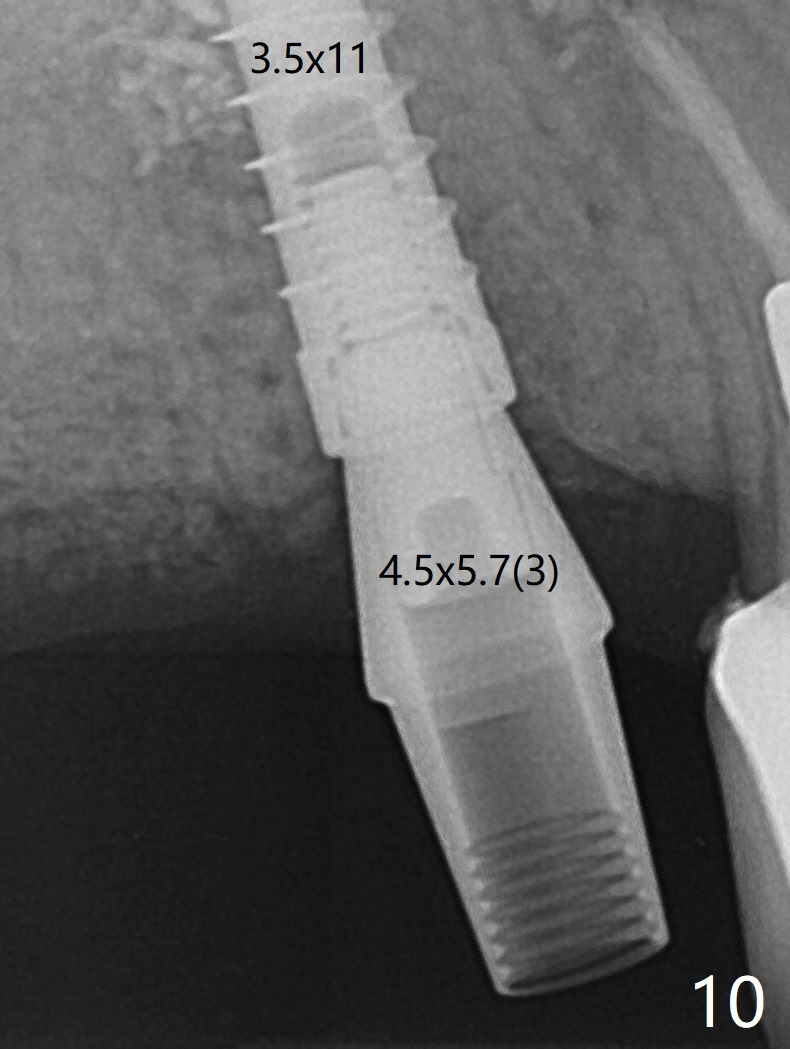

The patient returns for #4 extraction and immediate implant the 1st day clinic reopening after coronavirus lockdown. To reuse autogenous bone for #4 buccal gap closure, delayed implants are also placed at #13 and 14. It is much easier to determine the placement level of the immediate implant (open socket) with guide than that of the delayed ones (flapless) clinically. Immediate postop CT is taken for implant placement level confirmation (Fig.1-3). In fact the autogneous bone is too soft to be packed into #4 socket gaps. It has to be mixed with allograft to be packable. There is oozing when #14 healing abutment is placed. The hemorrhage is severe 4 days postop. The healing abutment is replaced by a healing screw. Hemostasis is achieved when the access is closed with GEM Cap and 4-0 Chromic gut suture. The patient will return for #3 extraction and socket preservation 1 month postop (Fig.4). To prevent postop hemorrhage, a cemented or temporary abutment will be placed at #4 before anesthesia, while .5 or 1.0 cc Augma bone will be placed at #3, covered with collagen plug and acrylic. In fact he cancels the appointment once because of symptom relief and will return 2 months postop. Sticky bone (Fig.5 *) and PRF is used at #3 for hemostasis, while a 5x5.7(3) mm pair (final) abutment is used to hold acrylic dressing in place. The latter remains in place with good oral hygiene 1 month postop (Fig.6 A: abutment). When the acrylic dressing is removed, the socket heals (Fig.7 K: the gingiva between the buccal and palatal sockets when the tooth was removed). The patient returns for impression 4.5 months postop. When the 5x5.7(3) mm abutment at #4 is reseated after cleaning, there is no horizontal gap between the abutment and implant in BW (Fig.8), while there is in PA (Fig.9). When a smaller abutment is seated (Fig.10), there appears to be a horizontal gap, whereas there is no vertical one. The situation is the same with #13 (Fig.11,12). The common denominator is 3.5 mm implant. With suspicion, BW is taken for the implant at #4 immediately before cementation (Fig.13). It appears that the abutment is most likely seated completely. There is no bone loss or screw loosening 4 months post cementation (Fig.14,15). One month later the patient agrees to have 3 lower implants to replace RPD.